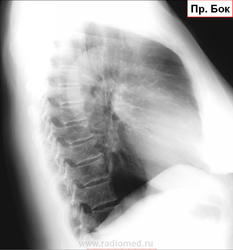

Снимки из серии "найти на боковой". Женщина 1948 г.р. Жалоб со стороны органов грудной клетки нет.Где тень на боковой проекции? К какому диагнозу склоняетесь? На днях будет ЛТ. ТМГ https://radiomed.ru/sites/default/files/styles/case_slider_image/public/user/16807/2_68.jpg?itok=PMWHQcLH https://radiomed.ru/sites/default/files/styles/case_slider_image/public/user/16807/3_42.jpg?itok=jjhsCDoN ID:46784 Fri, 25/04/2014 - 23:33 #1 алкс Offline Last seen: 10 years 6 months ago Joined: 24.10.2012 - 22:55 Posts: 2915 М.б. тутПриложения: Fri, 25/04/2014 - 23:38 #2 Сольвейг Offline Last seen: 3 years 11 months ago Joined: 05.02.2013 - 20:25 Posts: 2239 Ах, не успела. Тут, еще может в средней доле быть, -установка немного хромает. Рачок периферический, по-видимому, растет Fri, 25/04/2014 - 23:38 #3 NIL Offline Last seen: 3 weeks 1 day ago Joined: 25.11.2013 - 20:50 Posts: 18217 Да. Это она. Судя по гладкости и чёткости контуров, можно думать о доброкачественном новообразовании. Возможно, аденома.Приложения: "Слушай всех, прислушивайся к немногим, решай сам".© Fri, 25/04/2014 - 23:39 #4 Сольвейг Offline Last seen: 3 years 11 months ago Joined: 05.02.2013 - 20:25 Posts: 2239 А почему тмг не сейчас? Не сделали? Fri, 25/04/2014 - 23:57 #5 Dima Offline Last seen: 7 years 8 months ago Joined: 05.08.2012 - 17:39 Posts: 2467 Миргалина wrote: А почему тмг не сейчас? Не сделали?сделал, только карты открывать не хотелось сразу... Терпимость - это когда прощают чужие ошибки; такт - когда не замечают их. (Артур Шницлер) Sat, 26/04/2014 - 00:00 #6 Сольвейг Offline Last seen: 3 years 11 months ago Joined: 05.02.2013 - 20:25 Posts: 2239 Да открывайте уж, интересно же.Пожалуйста! Sat, 26/04/2014 - 00:15 #7 Dima Offline Last seen: 7 years 8 months ago Joined: 05.08.2012 - 17:39 Posts: 2467 Тень там где её и указали коллеги. Глазастые все, молодцы, а я вот долго искал...Приложения: Терпимость - это когда прощают чужие ошибки; такт - когда не замечают их. (Артур Шницлер) Sat, 26/04/2014 - 00:12 #8 Сольвейг Offline Last seen: 3 years 11 months ago Joined: 05.02.2013 - 20:25 Posts: 2239 Ну да, в 10-ке. Спасибо! Sat, 26/04/2014 - 10:03 #9 NIL Offline Last seen: 3 weeks 1 day ago Joined: 25.11.2013 - 20:50 Posts: 18217 Тень плотная. Может оказаться и гамартохондромой. "Слушай всех, прислушивайся к немногим, решай сам".© Tue, 29/04/2014 - 00:37 #10 lady.zhaneta Offline Last seen: 1 year 7 months ago Joined: 06.07.2011 - 21:54 Posts: 232 Спасибо от тех ,кто учится читая ваши комментарии, и от себя лично)

М.б. тут

Да. Это она. Судя по гладкости и чёткости контуров, можно думать о доброкачественном новообразовании. Возможно, аденома.

Тень там где её и указали коллеги. Глазастые все, молодцы, а я вот долго искал...

Ну да, в 10-ке. Спасибо!

Тень плотная. Может оказаться и гамартохондромой.